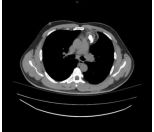

3. This 72-year-old diabetic man was taken to ER for productive cough for 10 days, and rapid progressive dyspnea for 2 days. He also had fever and chill for a week.